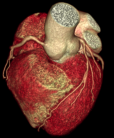

ANATOM P428 - CT Xoắn ốc 128 lát cắt

Khám phá kỷ nguyên mới của chẩn đoán hình ảnh y khoa với Hệ thống Chụp cắt lớp CT hiện đại 128 lát cắt, tích hợp liền mạch quy trình AI, tốc độ quay 0,33s/vòng và bóng tia X ổ trục kim loại 25MHU hiệu suất cao, hỗ trợ hơn 200 bệnh nhân mỗi ngày. Đỉnh cao công nghệ chẩn đoán này mang đến độ chính xác vượt trội trong các tình huống chăm sóc sức khoẻ tiên tiến